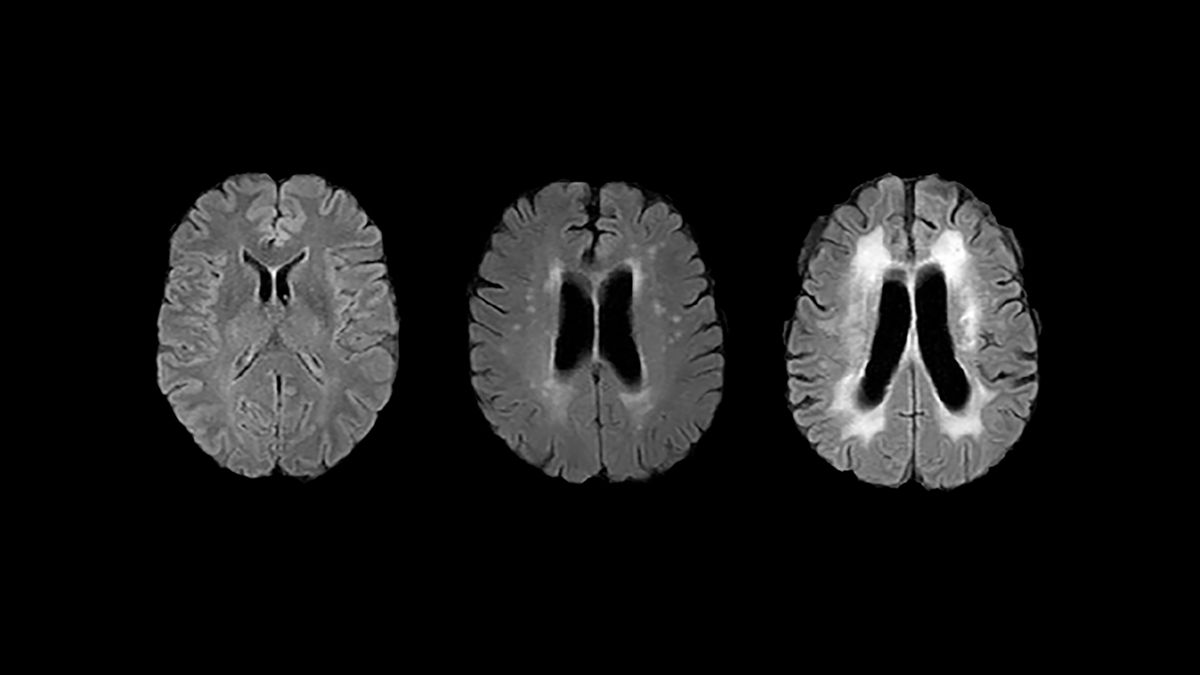

Pero si existe una diferencia entre los hombres y las mujeres, por ejemplo, los niveles de glucosa influyen más en la edad cerebral en los hombres. Se utilizaron modelos de inteligencia artificial de aprendizaje profundo para evaluar la edad cerebral a partir de exploraciones de resonancia magnética.